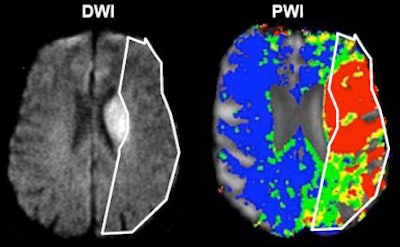

The original penumbra model relied on the mismatch between perfusion and diffusion on MRI -- the mismatched region representing the tissue you want to save, he said. In CT there is no diffusion, only perfusion, which is measured by mean transit time (MTT), cerebral blood flow (CBF), and cerebral blood volume (CBV). The way to distinguish potentially salvageable tissue from the infarct core in CT is by via cerebral blood volume and mean transit time through the cerebral vasculature, he said.

| Acute ischemic stroke visualized on diffusion-weighted MRI (left) and perfusion CT (right). All images courtesy of Dr. Max Wintermark. |